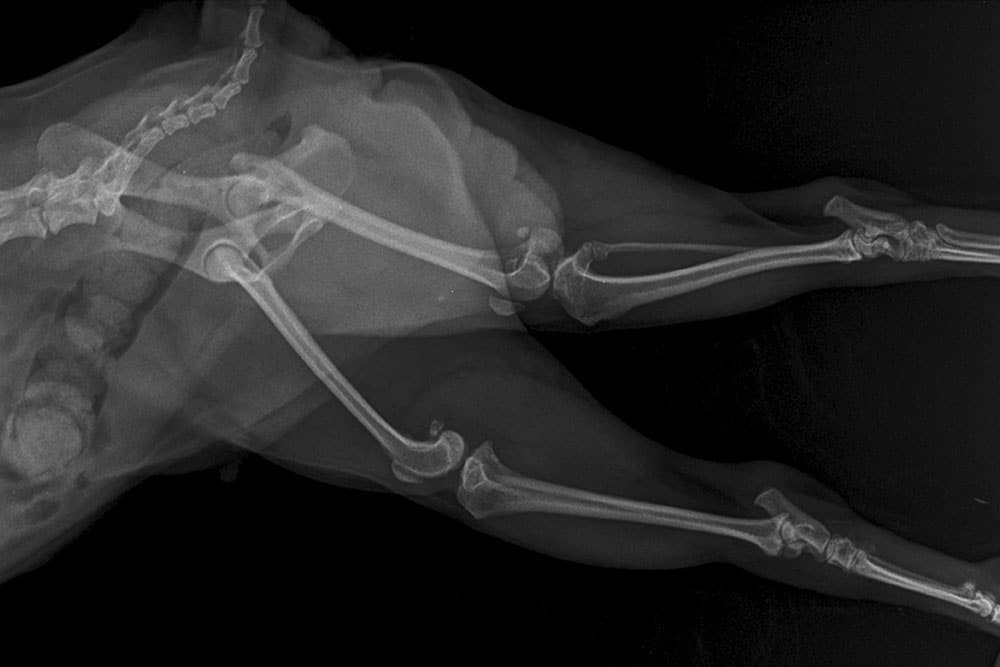

A lateral view X-ray showing the pelvis, hips, and hindlegs of a small animal, likely a cat or small dog.

X-ray imaging is great for checking the chest, abdomen, and bones. We use it to evaluate cough, heart size, breathing changes, or exercise intolerance; to look for masses, enlarged organs, or bladder stones; and to document arthritis severity. Baseline images make it easier to spot changes later.

Arthritis and mobility

Stiffness, slower walks, and trouble jumping often point to arthritis. X-rays confirm joint changes and help us plan support. A multimodal approach works best: anti-inflammatory meds, joint supplements, weight control, and targeted activity. Gentle exercises for osteoarthritis, home changes like non-slip rugs and ramps, and options like laser therapy can make a big difference in comfort and mobility.